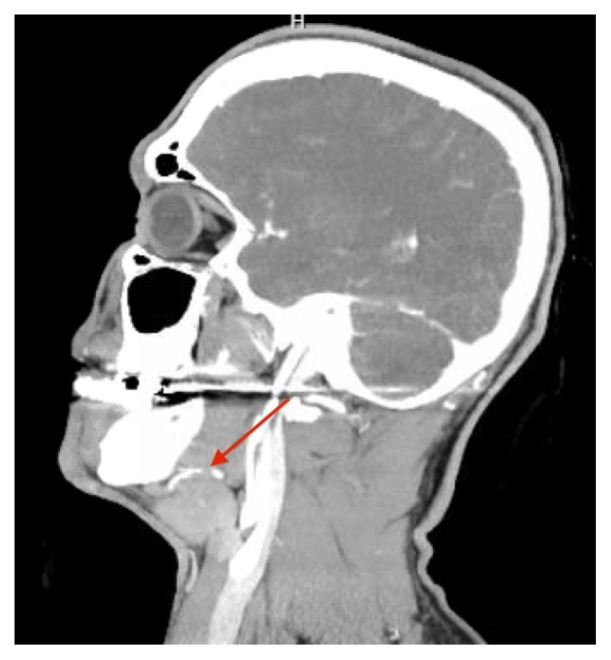

Traumatic Facial Artery Dissection from Chinstrap Injury: A Case Report.

Abstract Image